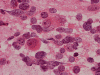

The volume of tissue received for examination amount to an aggregate of 4.0 x 2.0 x 1.5 cm in combined size. Grossly, the tissue is soft and has a creamy color with hemorrhage. The intraoperative cytologic preparation demonstrate a neoplasm composed with small to medium sized blue cells that smear out rather homgeneously and evenly. If you pay attention, there are some larger cells with a substantial amount of cytoplasm even at low magnification (Panel A). On high magnification, the nuclei are rather uniformly large, with high grade of pleomorphism, and almost all cells contain a distinct nucleoli. Apoptotic bodies and mitoses are frequent (Panel B). There are also large cells with prominent nucleoli and substantial amount of eosinophilic cytoplasm. These cells are suggestive of rhabdoid cells but none of them have the distinct inclusion body like cytoplasmic eosinophilic body of the rhabodid cells in atypical teratoid rhabodid tumor (Panel C). In the frozen section, both small to medium sized cells and cells with large nuclei with large, prominent, and eosinophilic nucleoli (Panel D and E). In the permanent sections, there is extensive necrosis (Panel F). The histology is in general agreement with that of frozen section except that the tumor cells appear to have more cytoplasm and more plemorphic, large nuclei with prominent nucleoli in comparison to the frozen section (Panel G). Large cells with substantial volume of cytoplasm, large, bizarre nucleoli and prominent, eosinophilic nucleoli are also noted (Panel H). There is a generalized degree of high grade pleomorphism. Results of immunohistochemistry are as follow:

Large cell and anaplastic medulloblastomas are recognized as different variants in the new WHO classficiation 1. They share many basic features with medulloblastoma 2, 3. The most notable differences are large cell size, increased variation of nuclear size, prominent and even eosinophilic nucleoli, increased mitotic figures and number of pyknotic or apoptotic cells, and extensive, geographic areas of necrosis. In the experience of the authors, most of the tumor cells in large cell and anaplastic medulloblastomas have high nuclear to cytoplasmic ratio in a manner similar to that of the classic variant. As per the new WHO classification, large cell medulloblastomas are composed mainly of large cells with more cytoplasm than the classic variant or the anaplastic variant. In the experience of the authors, this distinction is not always possible. The case being illustrated here includes some large cells with substantial amount of cytoplasm and but these cells only represent a portion of the tumor cell population. In general, anaplastic and large cell medulloblastomas have less favorable prognosis than the classic variant of medulloblastoma. However anaplastic changes are uncommon and does not affect the prognosis in adult cases as per one study 4.

ATRT shares many features with large cell (anaplastic) medulloblastomas. First, most of them occur in infants and children but ATRT are a lot more common in children under three years of age. Both tumor are highly malignant. In fact, the rapid growth as documented in this case lead to the consideration of ATRT before surgery. Second, both entities are featured by large cells with large nuclei and prominent nucleoli. During frozen sections, it may be a difficult task to distinguish these tumors. The rhabdoid cells in ATRT my not be very characteristics and a medulloblastoma like component is not uncommon in ATRT. Also, the rhabdoid cells may not be that numerous and the pathologist has to search for them. The intraoperative cytologic preparations provide excellent cytologic and nuclear details. In general, cells of large cell medulloblastoma do not have the typical eccentric nuclei and cytoplasmic inclusion like bodies in comparison to ATRT. In addition, although the nucleoli are large, they are not as prominent and eosinophilic as in ATRT. Third, cells of ATRT tend to be more intact and large cell (anaplastic) medulloblastomas tend to have predominantly naked nuclei. Distinction of the two entities on permanent sections is usually not a major problem. It should be noted that ATRT are polyphenotypic. However, they are usually positive for EMA which is typically negative in medulloblastoma and its variants. The greatest help would be immunohistochemistry for BAF-47. This antibody recognizes the protein coded by INI1 gene which is the critical gene on chromoome 22q11.2. This gene is expressed in normal tissue as well as neoplastic tissue except in the tissue where this gene is deleted and ATRT is the prototype 9. In some cases of ATRT, the staining can be patchy. The genetic deletion can be confirmed by fluorescent in situ hybridization. In a minority number of cases, no chromosome 22q11.2 deletion is demonstrated. The gene can be sequence in order to search for mutation of the INI1 gene.